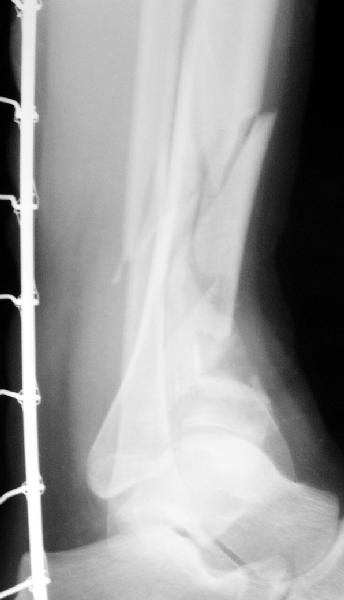

Re: Открытый оскольчатый внутрисуставной перелом д

Возможный альтернативный способ : накостный остеосинтез м/берцовой кости, открытый чрескостный остеосинтез эпиметафиза б/берцовой кости.